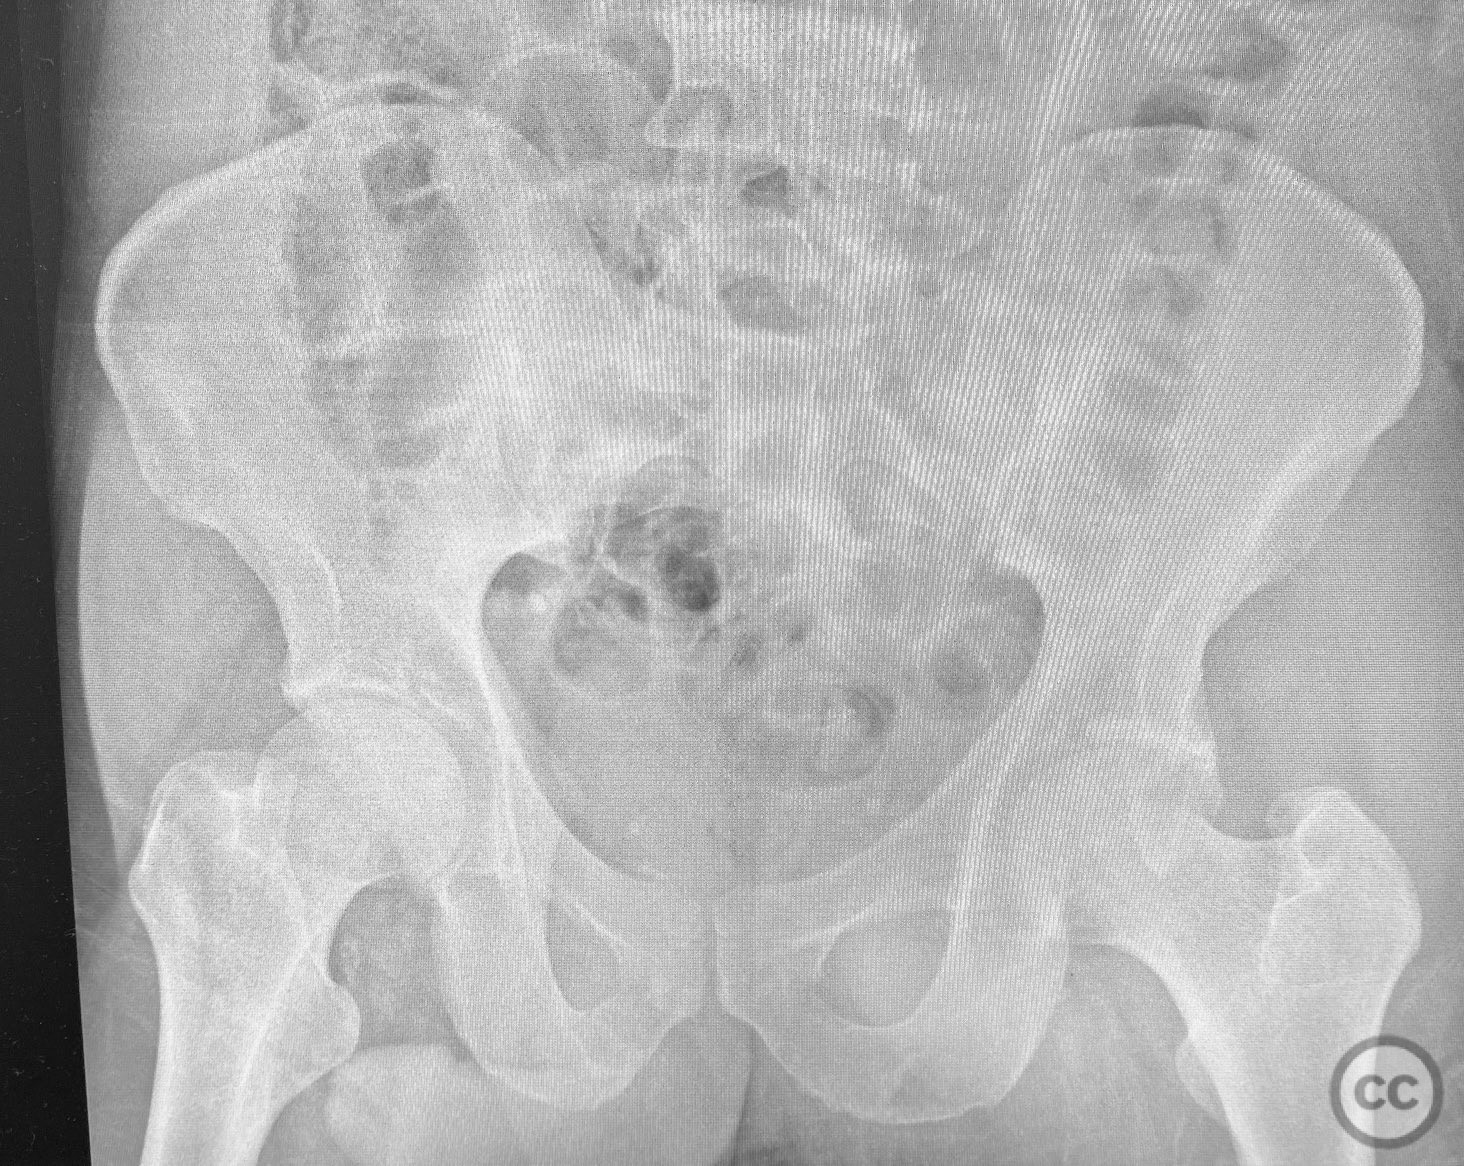

Clinical and radiological findings:  A patient presented with a seemingly non-comminuted, wide, and long posterior wall (PW) acetabular fracture fragment. Axial computed tomography (CT) images demonstrated the thickness of the PW fragment, the articular surface, and multiple areas of subchondral impaction. Preoperative planning identified the size, location, and depth of the impaction zones, as well as an essentially nondisplaced transverse acetabular fracture line, which was not readily apparent on initial imaging. No significant displacement of the transverse component was noted. The AO/OTA classification is 62-B1.3 (posterior wall and transverse acetabular fracture).